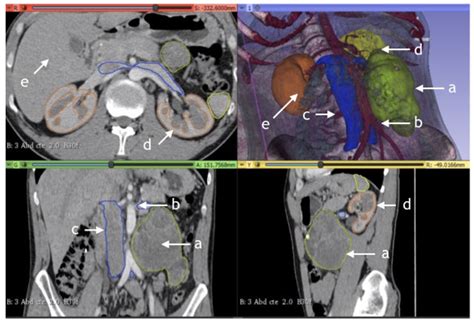

The Retroperitoneal Lymph Nodes are positioned in the posterior part of the abdomen, specifically within the retroperitoneal space. This area is situated between the posterior parietal peritoneum and the posterior abdominal wall. Unlike superficial nodes that can be felt near the surface of the skin, these nodes are deep-seated, making them invisible to the naked eye and difficult to palpate during a standard physical examination.

These nodes are organized into several major groups, primarily categorized based on their proximity to major blood vessels:

• Para-aortic nodes: These are located along the abdominal aorta.

• Pre-aortic nodes: Positioned in front of the aorta.

• Retro-aortic nodes: Situated behind the aorta.

• Paracaval nodes: Found alongside the inferior vena cava.

The drainage patterns of these nodes are highly specific, as they receive lymph fluid from various abdominal organs, including the kidneys, testes, ovaries, and the adrenal glands. Because they are the primary drainage route for these vital organs, they are frequently monitored during medical imaging.

• Computed Tomography (CT) Scans: The gold standard for visualizing these nodes. They provide detailed cross-sectional images of the abdominal cavity.